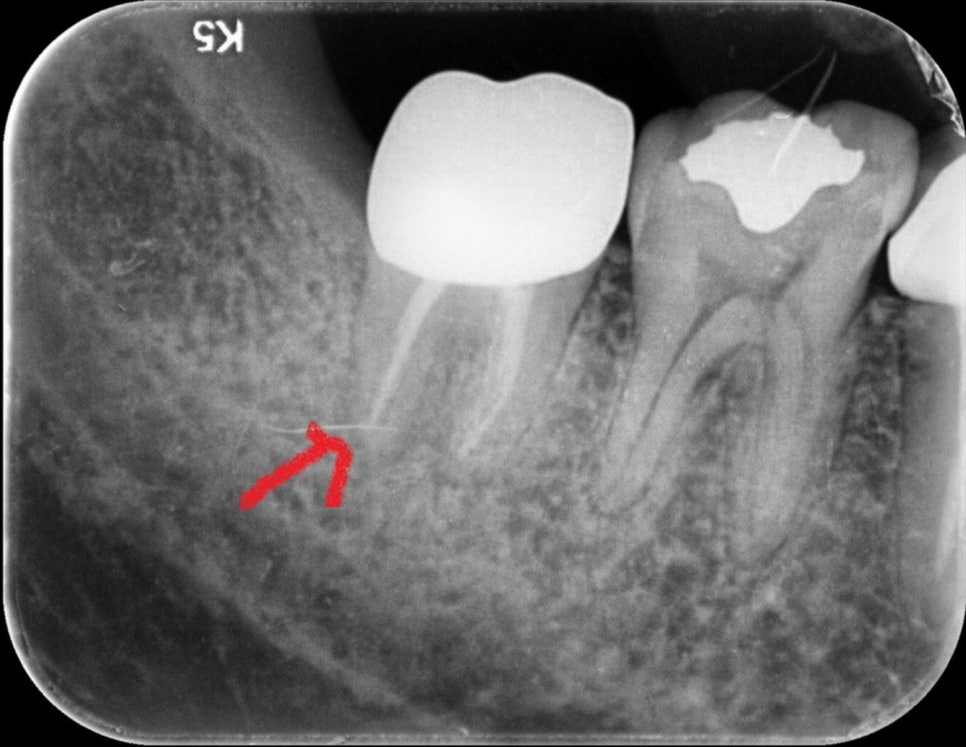

재식 _중 사진

다소 혐오스러울 수 있지만 건강하게 치아의 손상 없이 재식할 치아를 발치합니다.

재식 중 뿌리 끝 염증과 부근관 제거 모습

발치된 치아의 문제 부위인 염증과 부근관을 제거하였습니다.

MTA로 뿌리 부분 충전

제거된 뿌리 부분을 MTA라는 치과재료로 충전하여 다시 이식하게 됩니다.

재식_ 후 x-ray

위 사진은 이식 직 후 사진입니다. 이식 전 x-ray 사진과 비교해보시면 뿌리끝에 충전된 모습이 보이실 겁니다.